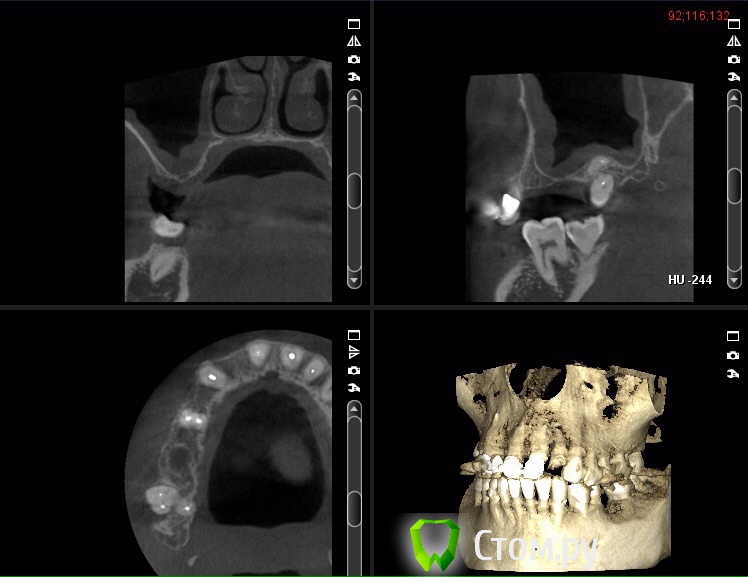

Фарид Расулыч Опубликовано 12 ноября, 2014 Поделиться Опубликовано 12 ноября, 2014 Есть пациент, человек, мужчина. Жалоб не предъявляет. Толщина в пазухе 5мм. Короткий вопрос: сначала лор потом синус? Ссылка на комментарий

Тимур86 Опубликовано 12 ноября, 2014 Поделиться Опубликовано 12 ноября, 2014 Кроме гипертрофии слизистой ничего не увидел...сразу синус имхо 2 Ссылка на комментарий

Фарид Расулыч Опубликовано 12 ноября, 2014 Автор Поделиться Опубликовано 12 ноября, 2014 В нагрузку Ссылка на комментарий

faity Опубликовано 12 ноября, 2014 Поделиться Опубликовано 12 ноября, 2014 если это не воспалительный процесс на данный момент, то работайте. до 10мм утолщение слизистой может быть, ничего страшного. Ссылка на комментарий

Bier Опубликовано 12 ноября, 2014 Поделиться Опубликовано 12 ноября, 2014 надо смотреть на соустье, если оно забито, то сначала к ЛОРу, а если свободно, то на синус ) 4 Ссылка на комментарий

Фарид Расулыч Опубликовано 12 ноября, 2014 Автор Поделиться Опубликовано 12 ноября, 2014 Так в том то и беда, что соустье не попадает в обзор... Ссылка на комментарий